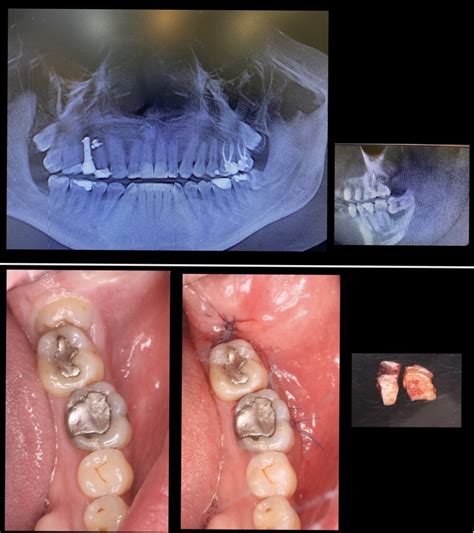

Si existe la necesidad de extraer las muelas del juicio, el odontólogo valorará si el procedimiento se puede realizar en la misma consulta dental. Esta intervención se realiza bajo anestesia local o general, dependiendo del caso y de las preferencias o posibles alergias del paciente. No, la extracción de la muela del juicio no es dolorosa ya que siempre se realiza bajo el efecto de la anestesia local. Además, siempre que el paciente lo pida, es posible solicitar la sedación consciente. Gracias a la sedación, se le induce a un estado de máxima tranquilidad y estará en todo momento bajo la supervisión de un médico anestesista.

El cirujano hace una incisión en la encía y retira el hueso que cubre la muela. Luego, extrae la muela entera o por fragmentos, y cierra la herida con puntos de sutura con mucha delicadeza.